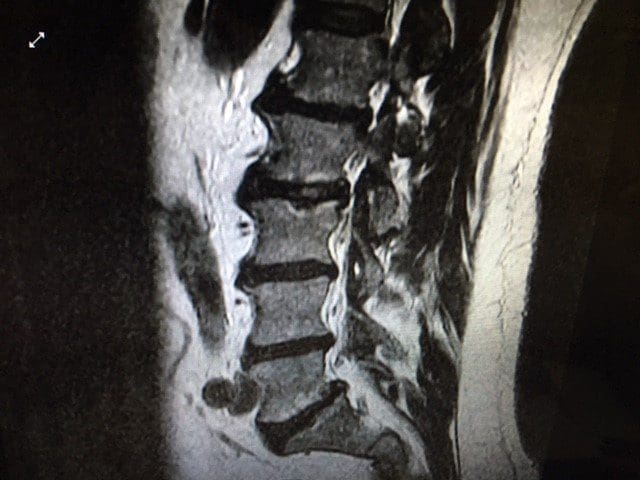

Lumbar MRI without contrast was ordered immediately with a 4 mm slice thickness and 1 mm gap in between slices on a Hitachi Oasis 1.2 Telsa machine for optimal visualization of pathology due to the clinical presentation of right L5 nerve root compression.

Lumbar MRI Imaging Results

- Significant degenerative changes throughout the lumbar spine including multi-level degenerative disc changes at all levels.

- Transverse Annular Fissures at L1-2 (17.3 mm), L2-3 (29.5 mm), L4-5 (14.3 mm) and L5-S1 (30.8 mm) and broad based disc bulging at all levels except L5-S1. The fissures at L2-3 and L5-S1 both have radial components extends through to the vertebral endplate.

- Facet osteoarthritic changes and facet effusions at all levels.

- Grade II spondylitic spondylolisthesis is confirmed at L5-S1 with severe narrowing of the right neural foramen compressing the right exiting L5 nerve root.

- Degenerative retrolisthesis at L1-2.

- Modic Type II changes at L2 inferior endplate, L3 superior endplate, L4 inferior endplate and L5 inferior endplate.2

- There is a 18.9 mm wide Schmorl’s node at the superior endplate of L3.

- There is a 5.7 mm wide focal protrusion type disc herniation at L4-5 which impinges on the thecal sac.

T2 sagittal Lumbar Spine MRI: Note the Modic Type II changes and the L2-3 Schmorls node.

T1 Sagittal Annular fissures at multiple levels and spondylolisthesis at L5S1